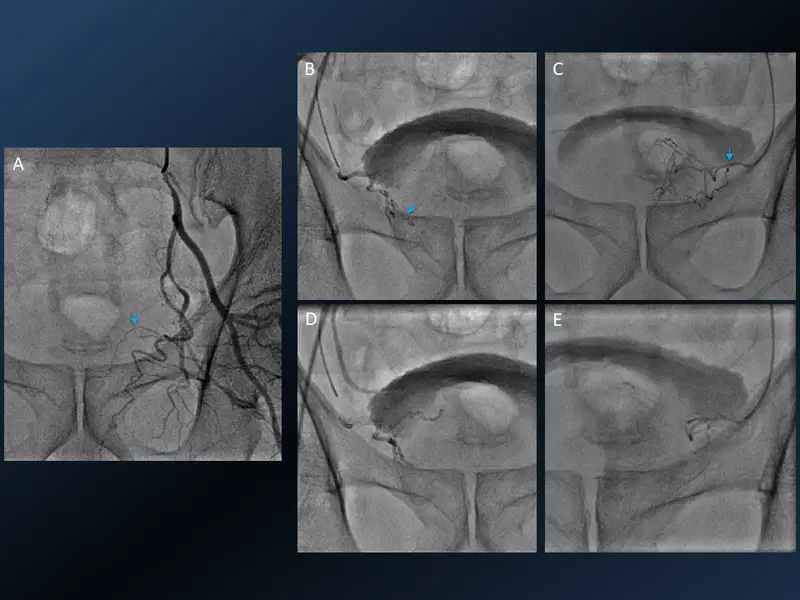

15. Prostate Artery Embolisation (PAE)

Prostate Artery Embolisation (PAE)

Elderly gentleman with LUTS. The anatomy of the prostate artery (arrow) is depicted in the left internal Iliac angiogram(A). Superselective cannulation and pre (B & D) and post (C & E) prostate artery embolization of both sides. Interesting similarity with UFE.